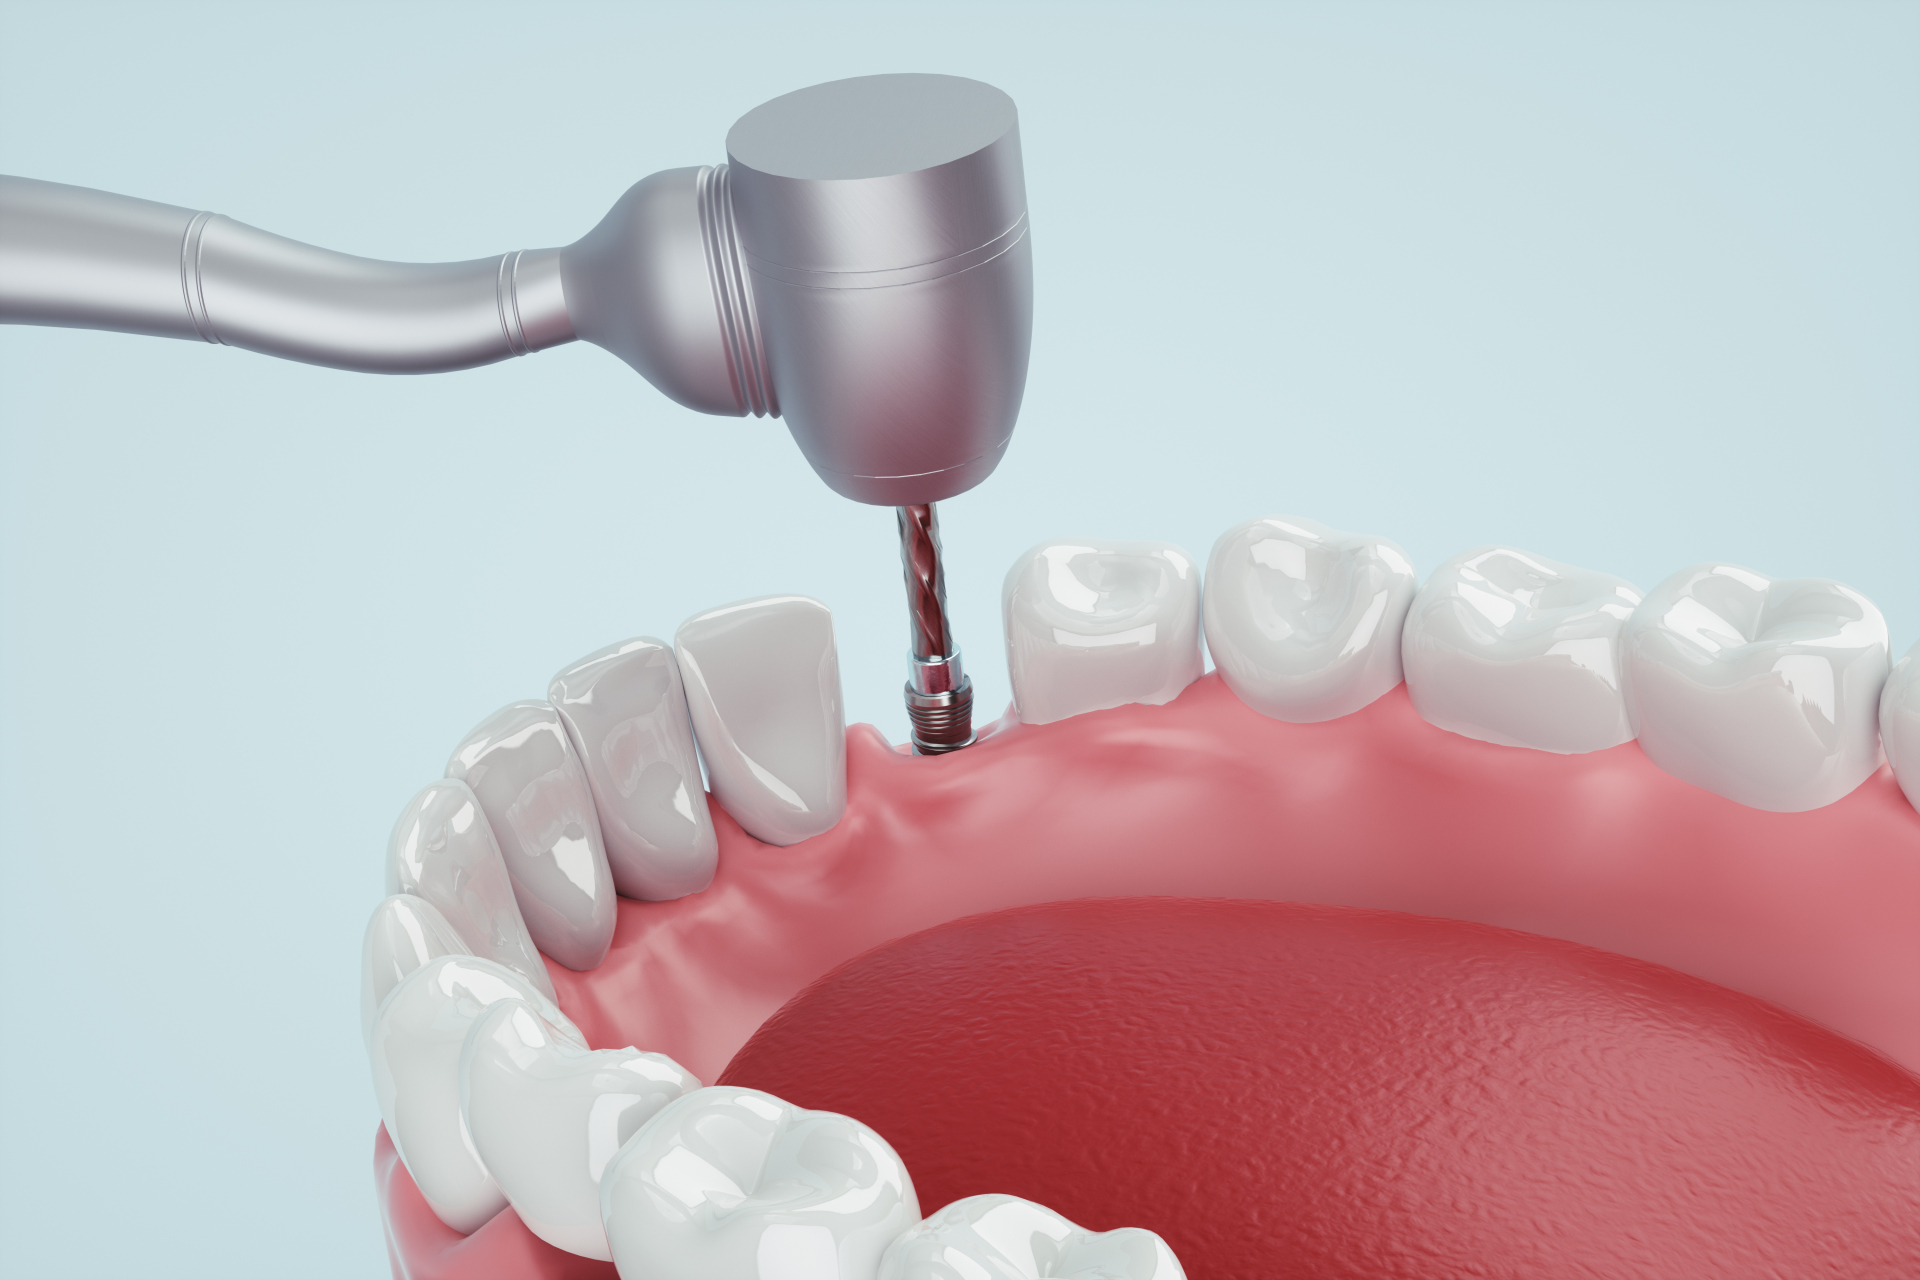

当院のインプラント治療

インプラント治療の流れ

インプラント1次手術

インプラント治療は専門性が高く、幅広い知識や高度な技術が求められます。